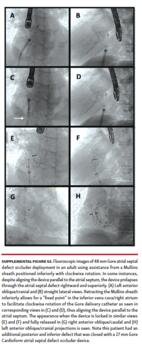

Mullins-sheath facilitated Gore Cardioform ASD occluder delivery technique. The mechanism of favorable exaggeration of the angle of the Gore Cardioform ASD occluder delivery system when used with a Mullins sheath is seen in Figure 1. In large defects or in defects with deficient rims, the angulation of the Gore delivery catheter may not allow for alignment of the device parallel to the atrial septum, with resultant device prolapse superiorly through the defect into the right atrium (Figure 2). In such situations, the short sheath was exchanged for an appropriately sized 63 cm-long or 75 cm-long Mullins sheath in the left atrium and the dilator and wire were removed (same Fr size as required short sheath Fr size). When used in combination with a Mullins sheath, the angulation is exaggerated enough to facilitate better alignment parallel to the atrial septum (Figure 3). The Mullins sheath was rotated clockwise to assume a posterior orientation to align the device parallel to the atrial septum as it was being delivered. The Gore Cardioform ASD occluder delivery catheter was then advanced through the Mullins sheath, which was positioned with continuous clockwise rotation, often by the assistant, as the primary operator deployed the device. In some cases, despite this maneuver, the device was not aligned parallel to the atrial septum. In such cases, once the left atrial side of the device was deployed and aligned in the best possible way, the Mullins sheath was withdrawn (if 63 cm-long sheath was used) to the inferior vena cava or right atrium to serve as a “fixed point,” whereby further clockwise rotation of the Gore delivery catheter could be performed if needed to facilitate further device alignment as parallel to the atrial septum as possible (Figure 4). In some cases, the Gore delivery catheter was rotated 180° clockwise despite the use of the Mullins sheath to facilitate capture of the aortic and superior vena cava rims. Use of the Mullins sheath also facilitated delivery of the device when inferior disc prolapse into the left atrium was encountered (Figure 5). Finally, in some cases, the tip of the Gore Cardioform ASD occluder delivery catheter was also hand-shaped to further exaggerate its angle. The use of the Mullins sheath was at the discretion of the implanting physician.

A total of 98 patients underwent attempted ASD closure during the study period (70 patients from the Gore ASSURED Clinical Study-Pivotal and Continued Access studies) and 28 patients after the study period. Of these patients, 52 underwent attempted secundum ASD closure using a long Mullins sheath (Supplemental Figures S1 and S2), while 46 patients underwent attempted secundum ASD closure with the Gore Cardioform delivery catheter through a short sheath in standard fashion.